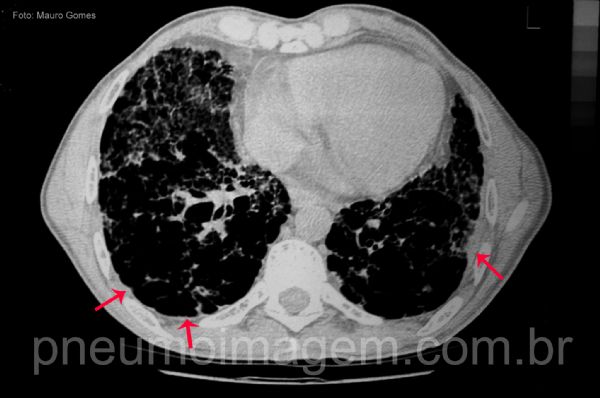

No mesmo corte, com janela para mediastino, pode-se observar o espessamento irregular da superfície pleural (seta).

In the same tomographic section, with a window for the mediastinum, the irregular thickening of the pleural surface (arrow) can be observed.

Chaves: espessamento de pleura; espessamento pleural; irregular thickening of the pleura (red).